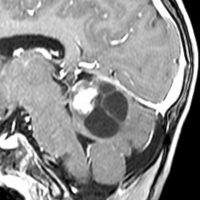

12歳の少女の小脳虫部と右半球深部白質の間にできた毛様細胞性星細胞腫 pilocytic astrocytoma です。軽い体幹失調がありました。のう胞壁の大部分には腫瘍はありませんが,一部に腫瘍壁があります。必ずしも境界は明瞭ではなく,小脳虫部の上内側面に広範囲に接着しています。年長児の毛様細胞性星細胞腫は,Rosental fiber, eosinophilic granular bodyが多く見られ,硬く,小脳脳組織に食い込み,簡単に剥離摘出できるものではありません。脳組織と切開切断するように切り落とさなければ全摘できないものです。

後頭下からみた腫瘍(緑)です。正中に大きな架橋静脈 vermian veinがあります。

この腫瘍を後頭下開頭で摘出しようとすれば,小脳虫部と右小脳半球の間をかなり長く縦切開しなければなりません。テント直下から小脳上面をたどっても腫瘍の上端は見えても摘出は不可能です。ですから,必然的にアプローチは後頭開頭経テント法 occipital transtentorial approachとなります。